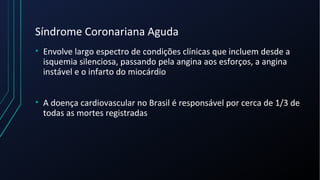

Dor torácica pode ter diversas causas, incluindo cardíacas como síndrome coronariana aguda, dissecção de aorta e pericardite, e não cardíacas como problemas pulmonares, musculoesqueléticos e do trato gastrointestinal. É importante avaliar a história clínica, características da dor e exame físico para identificar a possível causa e orientar o tratamento adequado.